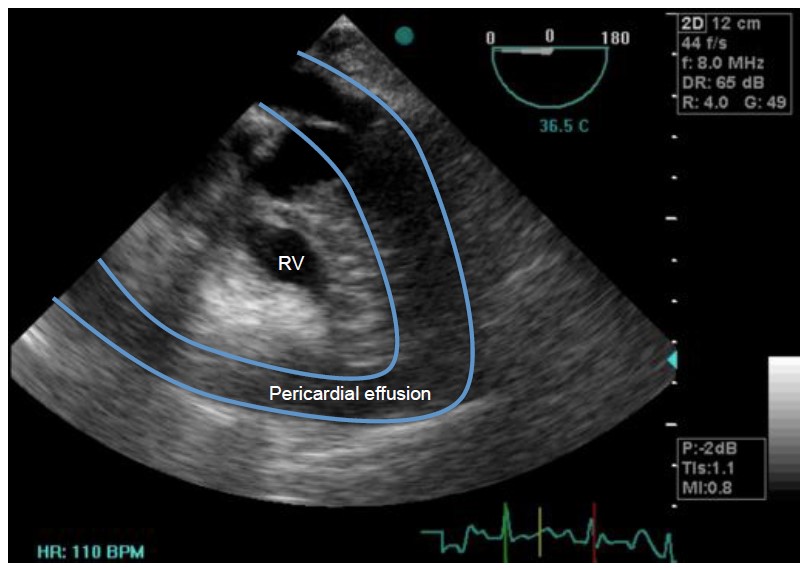

From www.researchgate.net

Echocardiography Showing Features of Cardiac Tamponade. Download How To Relieve Cardiac Tamponade Cardiac tamponade is the accumulation of pericardial fluid, blood, pus, or air within the pericardial space that creates an. Cardiac tamponade is a clinical syndrome caused by the accumulation of fluid, blood, pus, clots, or gas in. Cardiac tamponade is when fluid collects around the heart muscle, for instance, due to trauma. The only successful treatment is a hospital procedure. How To Relieve Cardiac Tamponade.